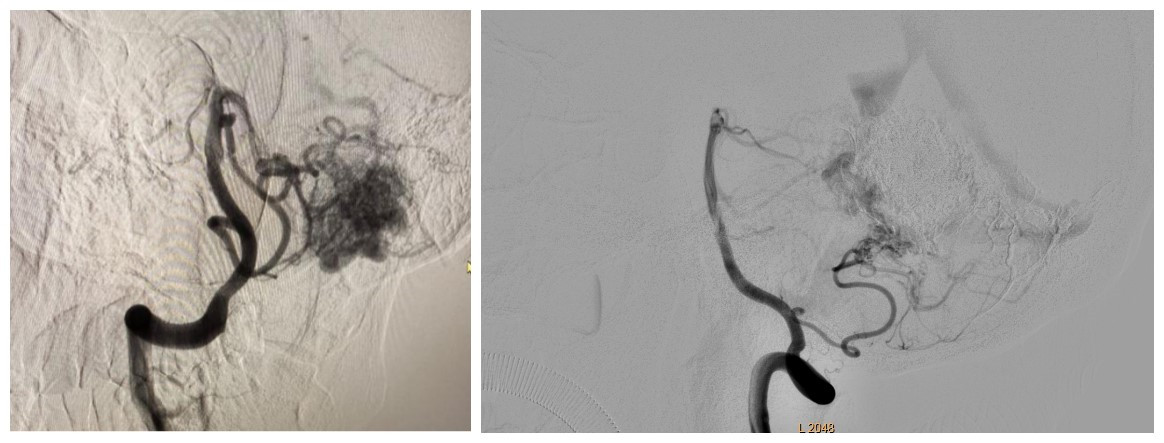

颅内动静脉畸形栓塞术

独立开展颅内动脉瘤、动静脉畸形、动静脉瘘、外伤性颈内动脉海绵窦瘘等介入栓塞治疗,已完成700余例,疗效显著。